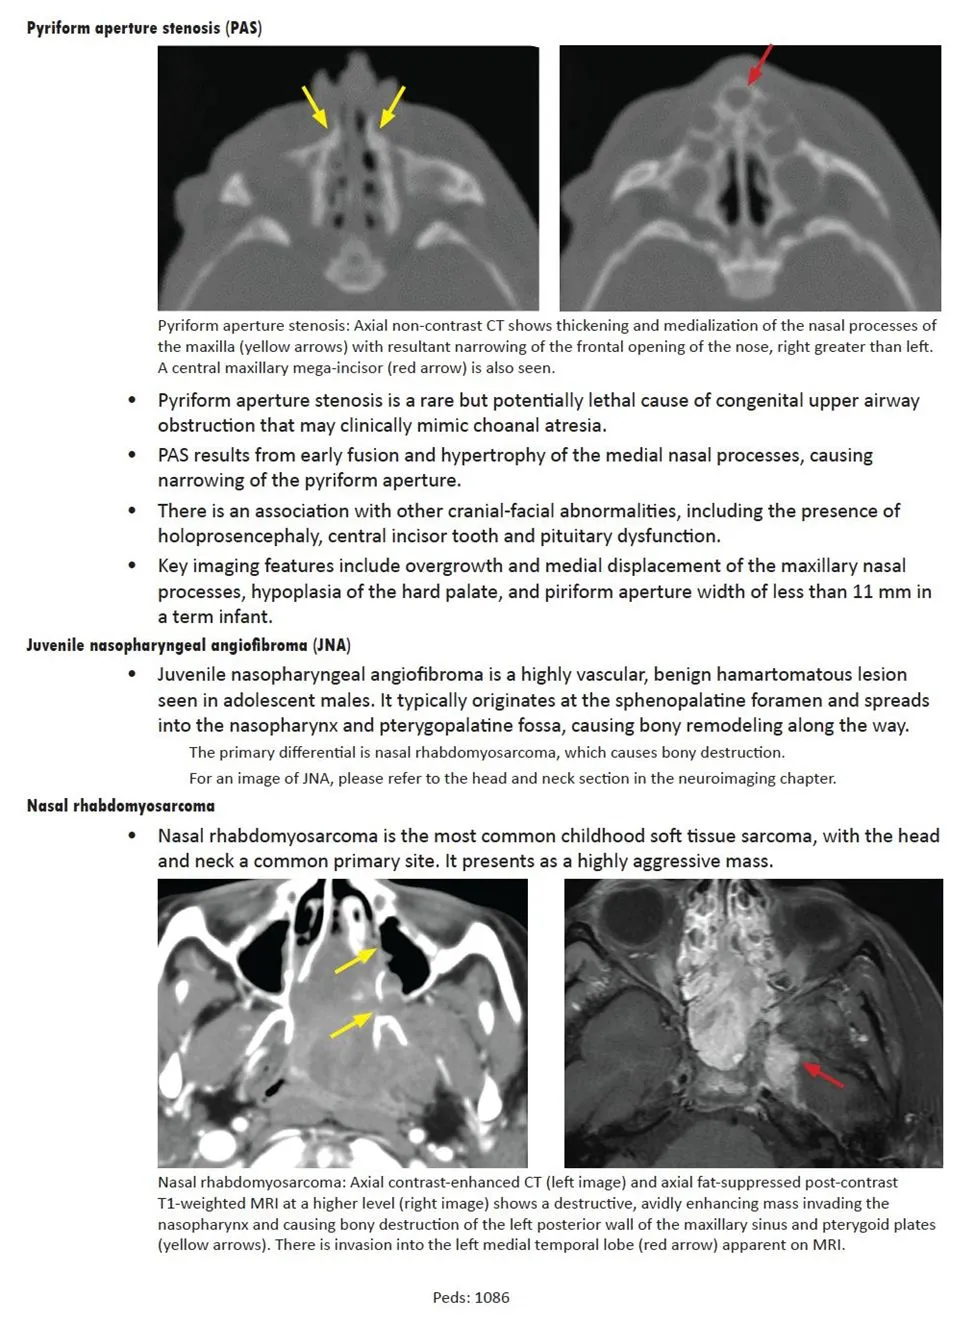

Juvenile nasopharyngeal angiofibroma commonly spreads from the sphenopalatine foramen into the {{c1::nasopharynx}} and {{c2::pterygopalatine fossa}} with associated bony remodeling

<b>Juvenile nasopharyngeal angiofibroma commonly </b>spreads from the sphenopalatine foramen into the {{c1::<u>nasopharynx</u>}} and {{c2::<u>pterygopalatine fossa</u>}} with associated bony remodeling